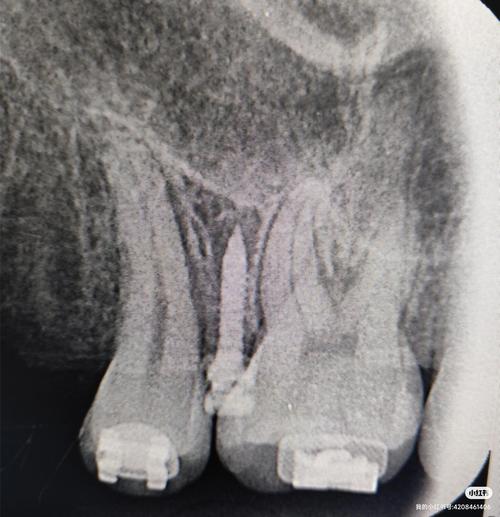

- 患者评估:通过口内检查、CBCT影像分析,明确牙槽骨厚度、密度、重要解剖结构(如上颌窦、下牙槽神经管)的位置,判断植入区骨量是否充足,上颌后牙区植入需避开上颌窦底,下颌颏部植入需注意颏孔神经位置。

- 术区定位与标记:利用口内照片或CBCT影像,在患者口腔内标记植入点(通常位于牙根之间或附着龈充足的区域),确保植入位置避开牙根(至少1.5mm距离)、牙龈系带及骨性凹陷。